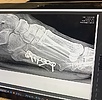

back at the beginning of february, while i was taking an after dinner walk while traveling for business to dallas, i stepped off a curb and landed on my face. when i got up, something wasn't right, and i grabbed a lyft back to my hotel and had a whiskey before nodding off to sleep. in the morning, i knew that i would not be able to wear the heeled boots that i had planned, and wore my tevas. after four hours of meetings, my left foot had swollen significantly and i decided to go to urgent care. long story short... i broke my fifth metatarsal and wasn't able to be load bearing for two months post surgery. i recently started walking again, and this little walk around the fence at humbolt mountain signified my first steps on uneven ground. so yes, i've been lurking. i missed spring with all of the zillions of flowers. i've been wondering how you all have been surviving without baseball. and i've had to live vicariously through you.